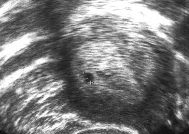

Schau mal, so hat es bei mir bei beiden ausgesehen in der 5. Woche (Foto ist aus der ersten SS vor 9 Jahren). Man sieht deutlich ein schwarzes Pünktchen innerhalb der GM. Ich denke, in der 5., 6.SSW sieht man sicher, ob es sich richtig eingenistet hat.